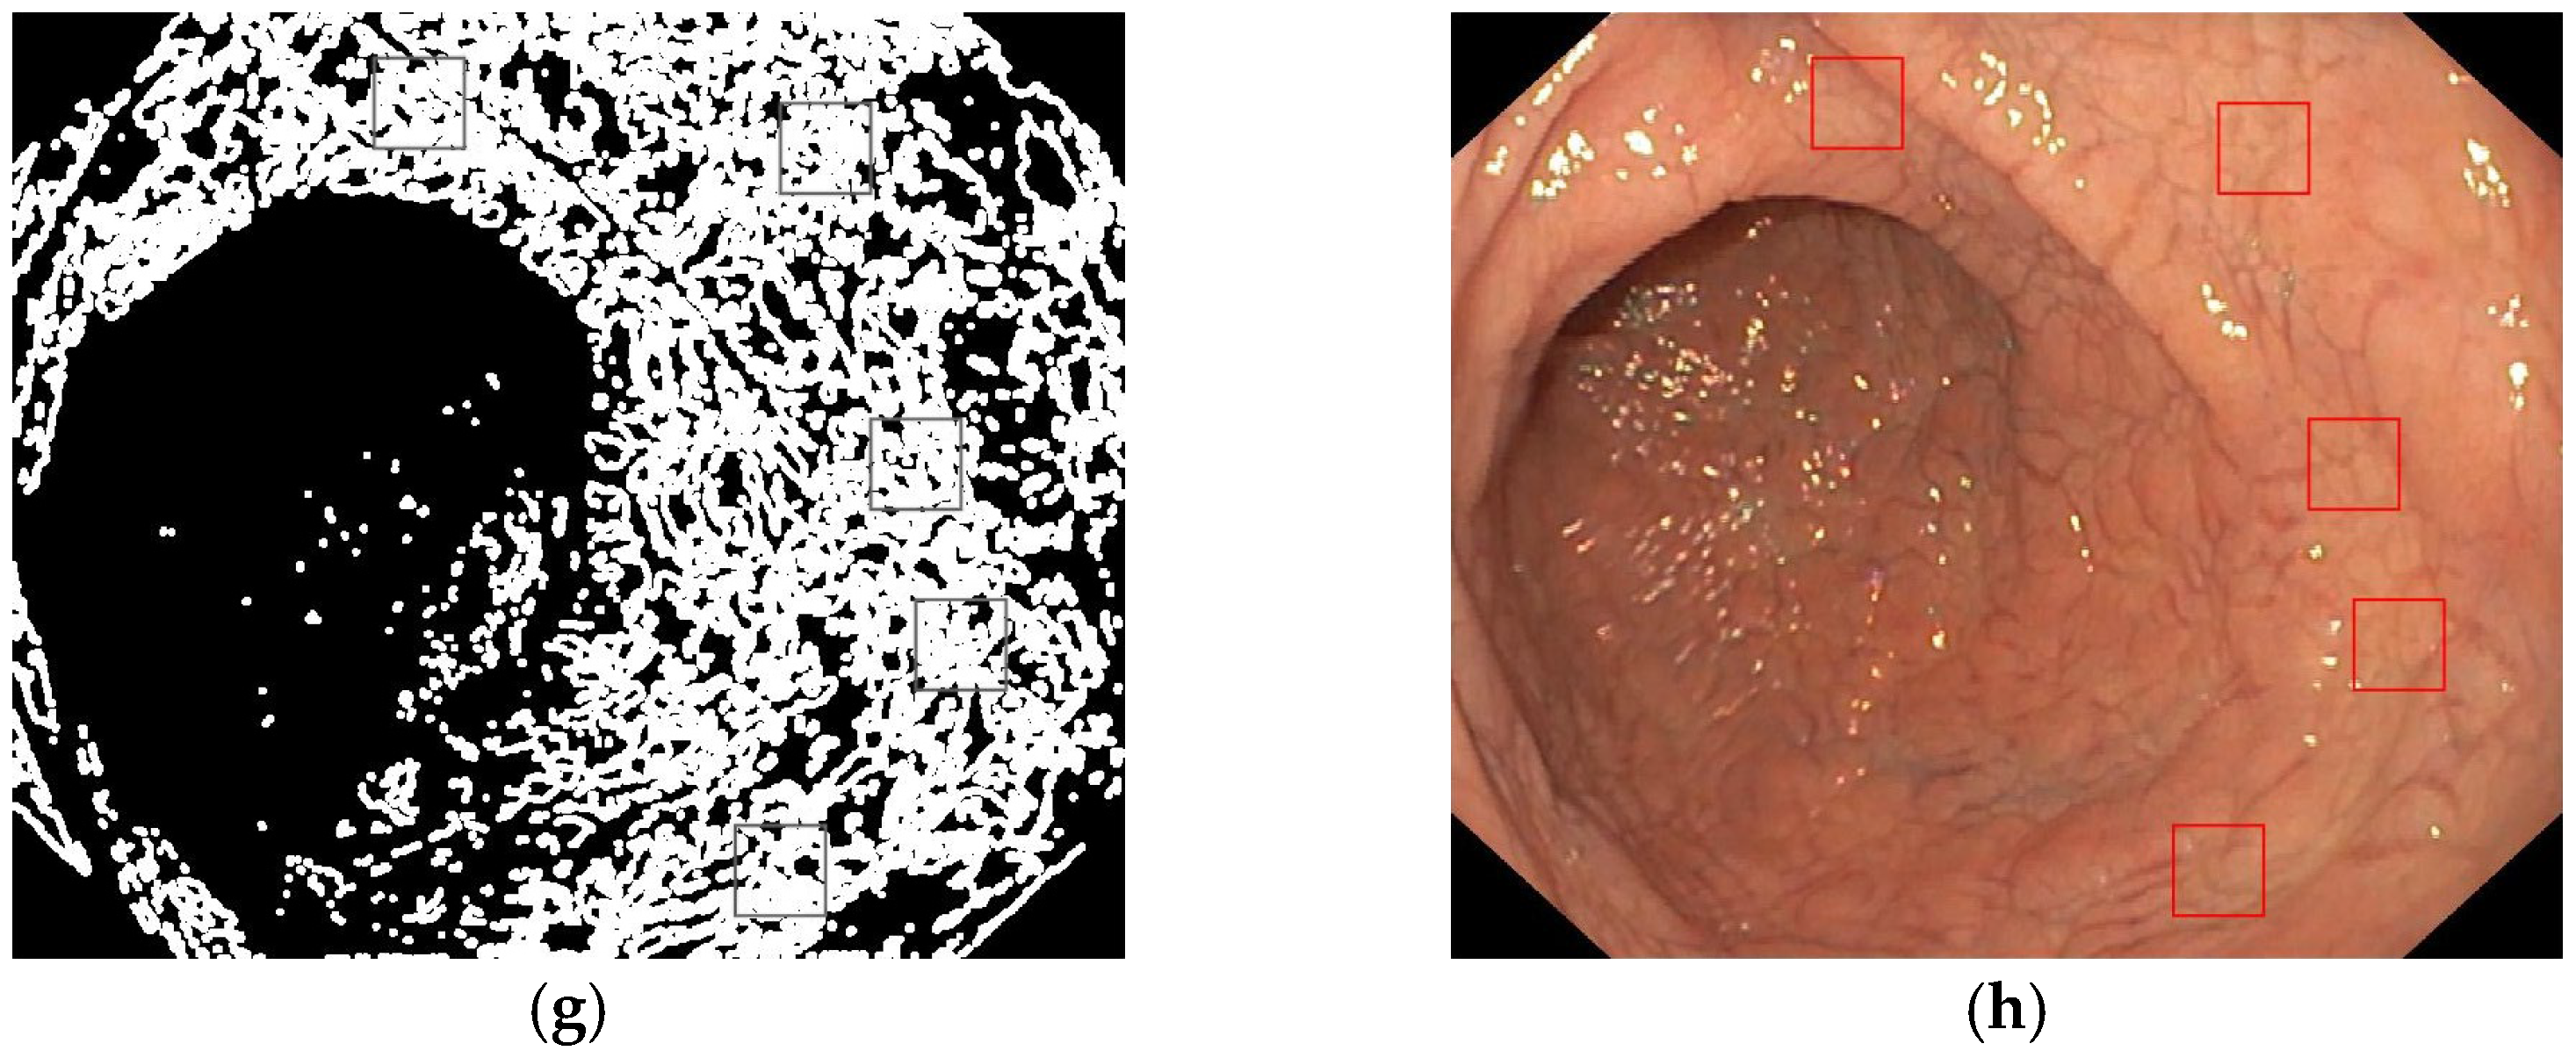

- Entropy filter applied on the gray level image;

- Binarization of the entropy-filtered image with high and low thresholds;

- Binarization of the gray level image using two high and low thresholds;

- Logic AND between binary images and dilatation;

- Patches selection according to the final binary image and the gray level range.